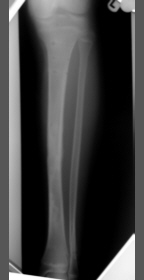

This is a 14 year old boy who caught his ski in the mesh of a dry ski slope and sustained a tibial fracture with a large anterior butterfly. This was stabilised with the Sheffield Hybrid Fixator. As the fracture line was very steep (81 degrees), additional fixation was required but safe soft tissue corridors contraindicated compressive olive wires, and so the arched wire technique was employed. Although immediate postoperative weightbearing was advised he was afraid to load the leg until one morning around 4 weeks post injury, where he suddenly found himself walking pain free. Since then, he was able to fully weightbearing without discomfort (picture taken at 6 weeks post-op). The arched wires and middle ring were removed for dynamisation at 11 weeks and the frame was removed at 15 weeks. He has had an excellent radiological and functional outcome. |